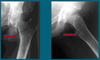

What are the radiographic features of developmental coxa vara?

[Lovell and Winter]

- Decreased femoral neck-shaft angle (<120o)

- Vertical position of physeal plate

- Triangular metaphyseal fragment in inferior femoral neck with associated inverted Y appearance

- Shortened femoral neck

- Decrease in normal anteversion